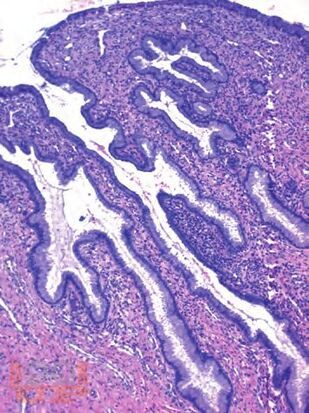

В практическом пособии рассматриваются основные принципы морфологического исследования при заболеваниях матки, гистофизиологические изменения шейки матки и эндометрия на протяжении менструального цикла и в разные возрастные периоды женщины, различные аспекты патогенеза и диагностические критерии доброкачественных и злокачественных поражений матки, значение иммуногистохимических исследований в интерпретации морфогенеза поражений и дифференциальной диагностики последних.

Особое внимание уделяется терминологии, приводится принятая в настоящее время гистологическая классификация опухолей шейки и тела матки (ВОЗ, 2014). Представлены также материалы, касающиеся состояния хориальной и плацентарной тканей при нормально протекающей и осложненной беременности, и современные сведения о гестационной трофобластической болезни.